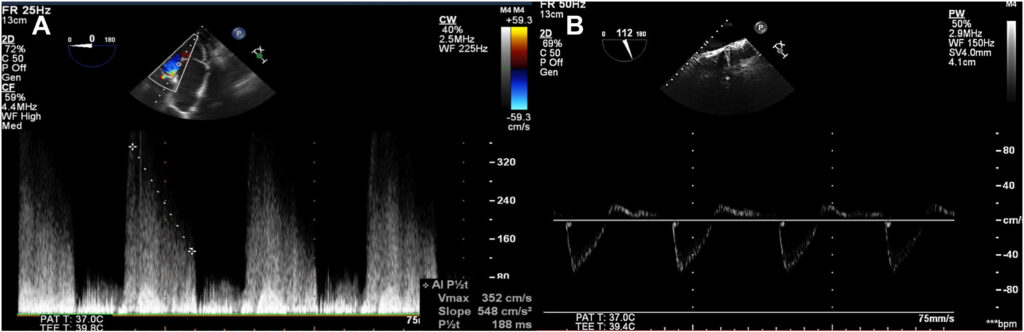

No terceiro dia de admissão, foi realizado ecocardiograma transtorácico cujo resultado demonstrou fração de ejeção (FE) de 60% e uma valva aórtica trivalvular com perfuração do folheto não coronariano e insuficiência aórtica (IAo).

A avaliação transesofágica mostrou um volume diastólico final indexado do ventrículo esquerdo de 47.00 ml/m², diâmetro diastólico final de 4.7 cm e aumento da raiz de aorta, com 3,7 cm no seio de Valsalva e 3.2 cm na região sinotubular.

Indicada abordagem cirúrgica e ecocardiograma transesofágico antes do procedimento mostrou prolapso do folheto coronariano direito, perfuração do folheto coronariano esquerdo e também no não coronariano, além de fluxo reverso holodiastólico em aorta descendente.